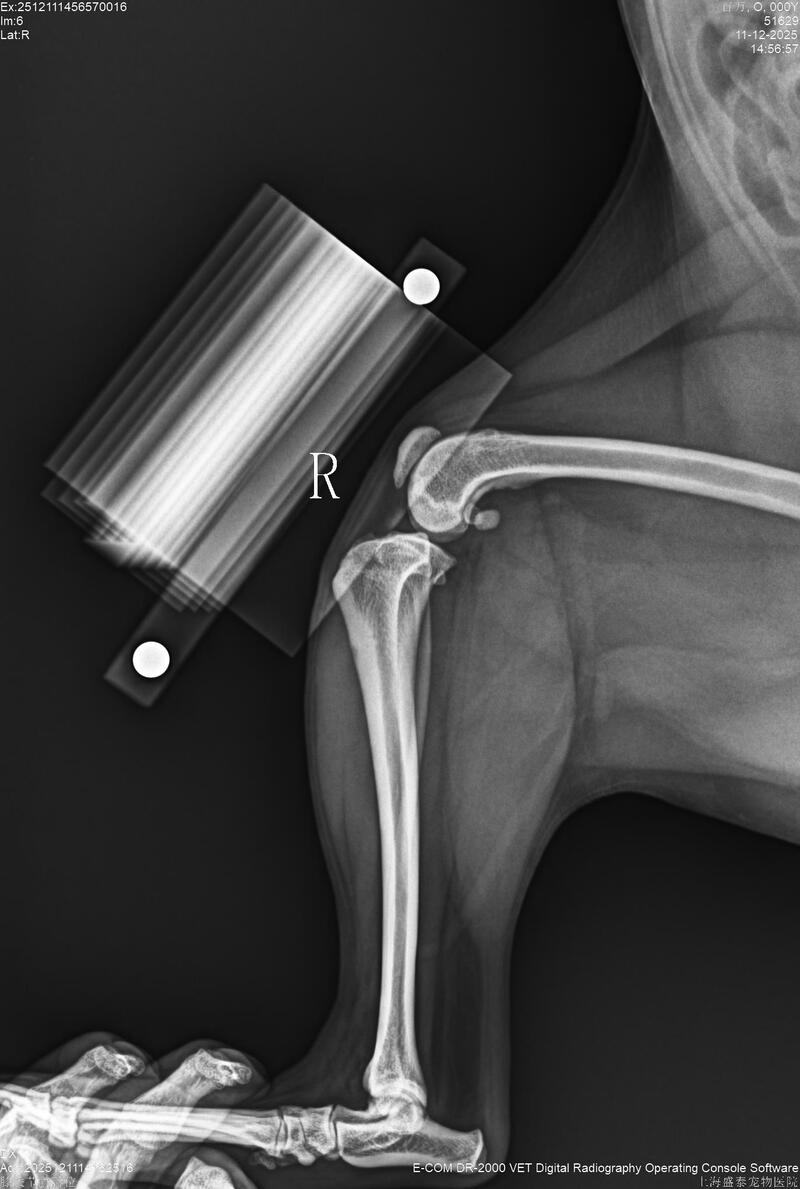

One week ago, the dog suddenly developed left hind limb lameness. The left anterior cruciate ligament was ruptured, and the left patella had a grade 4 dislocation, while the right patella had a grade 3 dislocation. A PGRand TPLO surgery was decided upon for treatment.

During the operation, the BlueSAObiologicalPGR system#4 implant was used for replacement, and the BlueSAOTPLO-7 mm L pure titanium locking plate was used for internal fixation. The surgery caused minimal damage, and the recovery would be faster. The dog was able to bear weight and walk 3 days after the surgery. Hope for a speedy recovery.